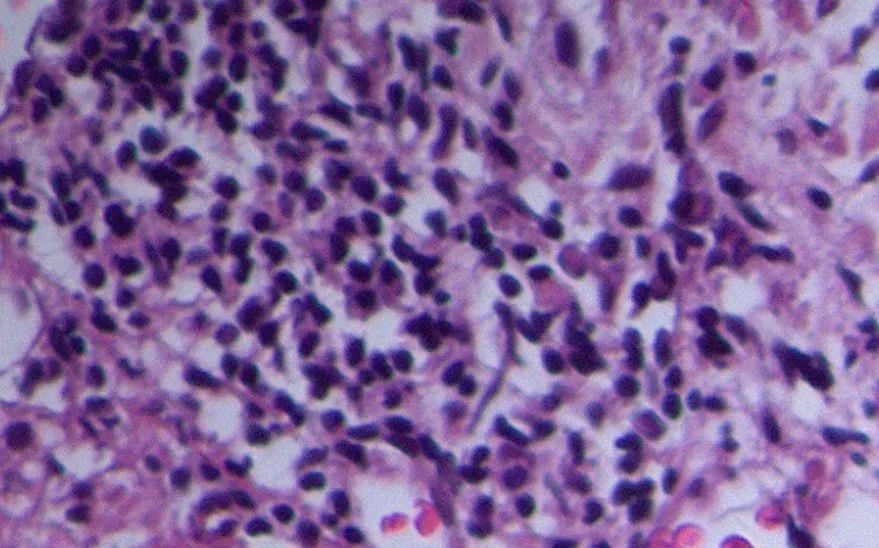

图5 患者的病理切片(注意红箭头和蓝箭头所指)

如图5,多个血管里出现异常组织(红箭头),并且有非常明显的有丝分裂,核异性(蓝箭头)。这不是肿瘤细胞吗?

因此,我们考虑“卵巢癌肝转移”。

我们认为,出现的混合炎症细胞浸润现象显然与肿瘤细胞在脉管的大量形成有关。